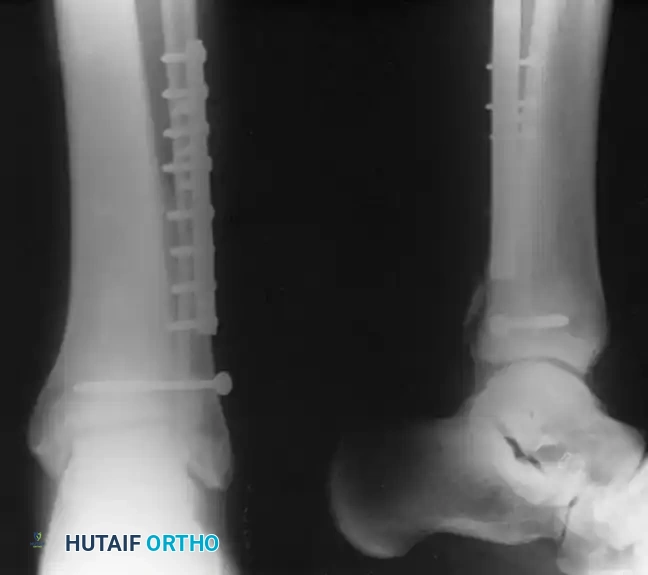

Operative Techniques for the Lateral Malleolus

- Lateral Plating (Neutralization): The standard approach utilizes a direct lateral incision. The fracture is anatomically reduced with pointed reduction forceps. An interfragmentary 3.5-mm lag screw is placed perpendicular to the fracture plane, followed by a 1/3 tubular neutralization plate applied to the lateral aspect of the fibula.

Surgical Sequence for Bimalleolar Fixation

- Lateral Side First: The fibula is typically addressed first to restore the length and rotation of the lateral column. This often indirectly reduces the talus and simplifies the medial reduction.

- Medial Side Second: Once the lateral mortise is established, the medial malleolus is directly reduced and fixed.

- Syndesmotic Evaluation: After bimalleolar fixation, the syndesmosis must be tested using the "Cotton test" (lateral traction on the fibula using a bone hook). If widening occurs, syndesmotic screws or flexible suture-button constructs are required.